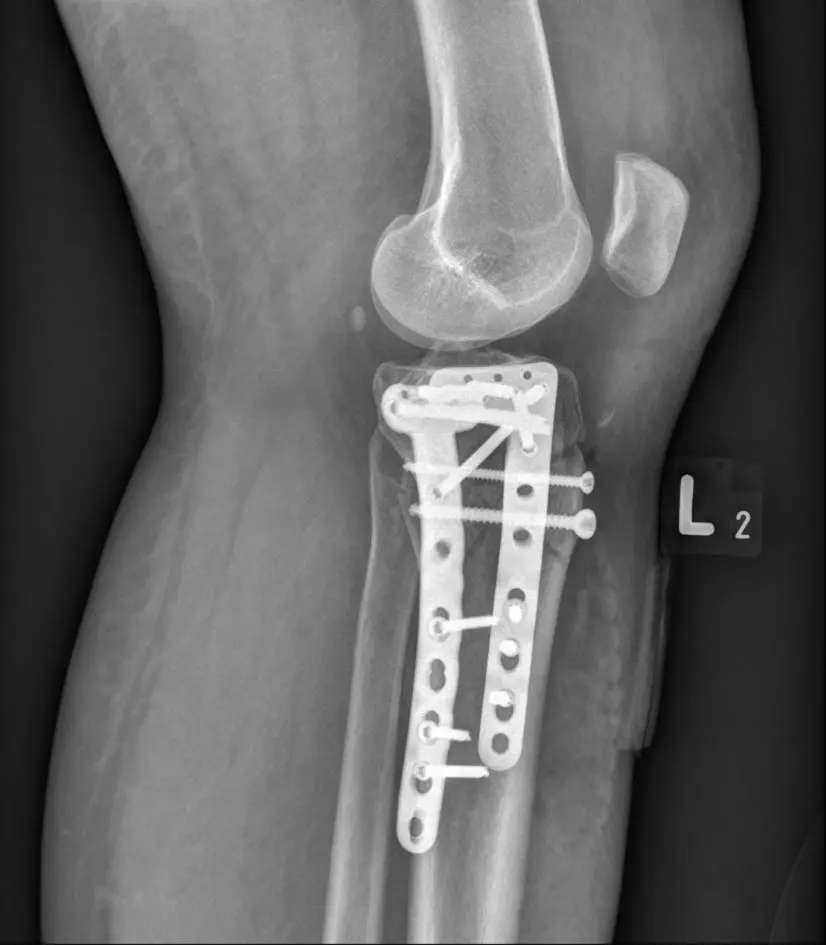

Zdjecie RTG Stabilizacja Zlamania Konca Blizszego Kosci Piszczelowej Po Wypadku Carolina Medical Center 826x945 1

Zdjęcie RTG - Stabilizacja złamania końca bliższego kości piszczelowej po wypadku.

Złamań najczęściej doznają dzieci – są to głównie złamania w okolicy połączeń pomiędzy więzadłem a kością, i tzw. złamania awulsyjne (gdy dochodzi do oderwania się fragmentu kostnego z przyczepem więzadła lub ścięgna). Dorośli najczęściej doznają urazów skrętnych.